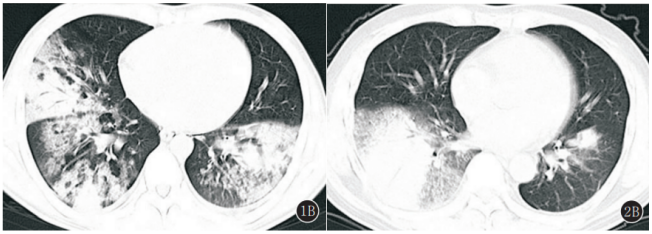

2018年1月至2020年12月我科数据显示,重症腺病毒肺炎好发于中青年男性(图2),不同病毒型的临床表现类似。图2 我科2018年1月至2020年12月重症腺病毒肺炎性别和年龄构成图重症腺病毒肺炎除了呼吸系统表现外,还会出现神经系统、循环系统、消化系统、泌尿系统、网状内皮系统及其他临床表现。呼吸系统主要表现为咳嗽、气促,发热,肺部体征出现晚,以及胸腔积液;神经系统主要表现为精神萎靡、烦躁与嗜睡交替,同时可以出现抽搐、昏迷、中毒性脑病、脑膜炎、脑水肿以及脑疝等;循环系统主要表现为心肌炎、心力衰竭、窦速,心电图T波或ST段改变;消化系统主要表现为呕吐、腹泻、中毒性肠麻痹、消化道出血;泌尿系统主要表现为蛋白尿、出血性膀胱炎;网状内皮系统可出现肝脾大、淋巴结增大表现;其他还有红色丘疹、斑丘疹、扁桃体石灰样小白点等表现。我科对重症腺病毒肺炎患者的统计分析发现,最常见的临床表现是发热、咳嗽、气促、咳痰(图3)。图3 我科2018年1月至2020年12月重症腺病毒肺炎患者症状分布直方图我科2018年1月至2020年12月重症腺病毒肺炎患者统计发现:①白细胞计数可正常,可升高(13%),也可降低(25%),淋巴细胞降低较常见(75%),血小板减少(25%);②心肌酶升高(100%):CK、CK-MB、LDH及MYO升高;③肝功能损害(56%):AST及ALT升高;④肾功能损害(25%):Cr和/或BUN升高;⑤同时存在肝肾功能损害(25%)。重症腺病毒肺炎患者胸部CT可见两下肺为主单发或多发叶段性实变伴或不伴磨玻璃影(GGO)(图4)[2]。国内文献报道了典型重症腺病毒肺炎的影像学,主要表现为实变、GGO、间质病变、胸腔积液(图5)[3]。我科统计重症腺病毒肺炎患者的影像学情况(图6):①双肺实变12例(80%),实变累及5个肺叶1例、累及4个肺叶5例、累及3个肺叶5例。②双肺实变伴GGO 5例(30%);③单肺实变3例(20%),均累及2个肺叶;④单肺实变伴GGO 3例(20%);⑤伴胸腔积液4例(25%),伴气胸1例(6%)。(1)症状:好发于中青年男性,有发热、咳嗽、呼吸困难、肌痛等表现。(2)影像学:实变伴或不伴GGO,伴胸腔积液;动态变化反映病情。